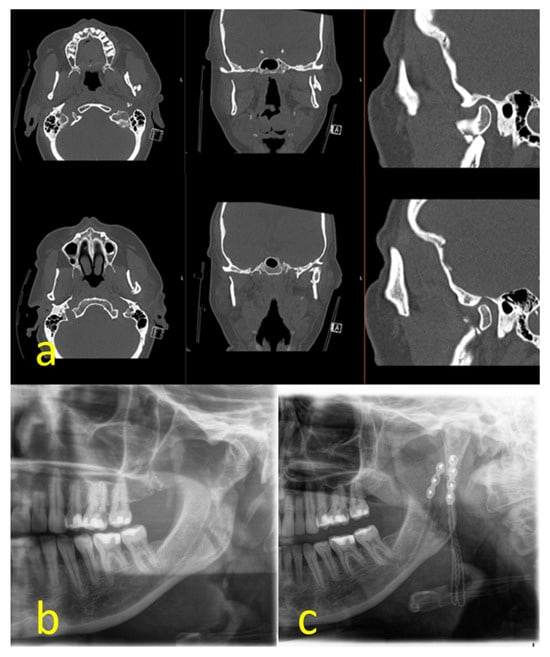

The cases could be subdivided in 62 unilateral and 53 bilateral fractures. A total of 107 of the 115 fractures were treated by ORIF (93.0%); 8 underwent conservative therapy (7.0%). Conservative treatment by intermaxillary fixation was carried out for a mean of 23.57 ± 10.37 days. According to the Spiessl and Schroll classification, the dominant type of fracture was type II (n = 61; 53.0%) (Figure 1a) followed by type III (n = 22; 19.1%), type I and V (n = 15; 13.0% each), and type IV (n = 2; 1.7%). Type I was present in 62.5% of conservatively treated fractures (n = 5), whereas 97.0% of the displaced or dislocated fractures underwent ORIF (n = 97) (Figure 1b). Type IV and V fractures exclusively received open treatment. This distribution was statistically significant (p < 0.001). A total of 15 fractures were classified as comminuted fractures by reference to preoperative 3D imaging (Figure 2a–c). A retromandibular transparotid approach was chosen in 93.5% of the open-treated cases (n = 100) (Figure 3a–f).

Figure 2. Comminuted type II fracture: CT-scan (a); preoperative panoramic x-ray (b); postoperative panoramic x-ray (c).